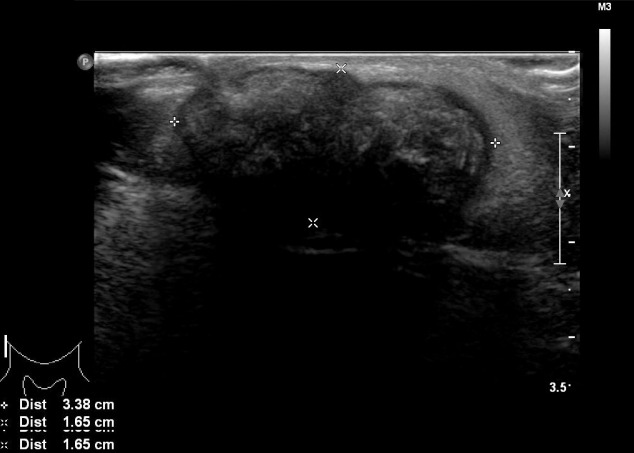

诊断时为35岁的张雨绮(女,化名)右侧腮腺区有肿块,就诊于佳学基因检测合作医院的整形外科。 肿块直径约 1 cm,张雨绮因无临床症状而拒绝手术切除。 然而,在怀孕的中晚期,肿块的大小增加到 5 厘米(图 1),并且变得疼痛。 分娩后肿块停止生长。 触诊肿块时,患者报告疼痛从腮腺区放射至耳后区。 病灶摸起来温暖、坚硬、淡蓝色和分叶状。 由于临床症状加重,患者同意接受手术切除肿块。